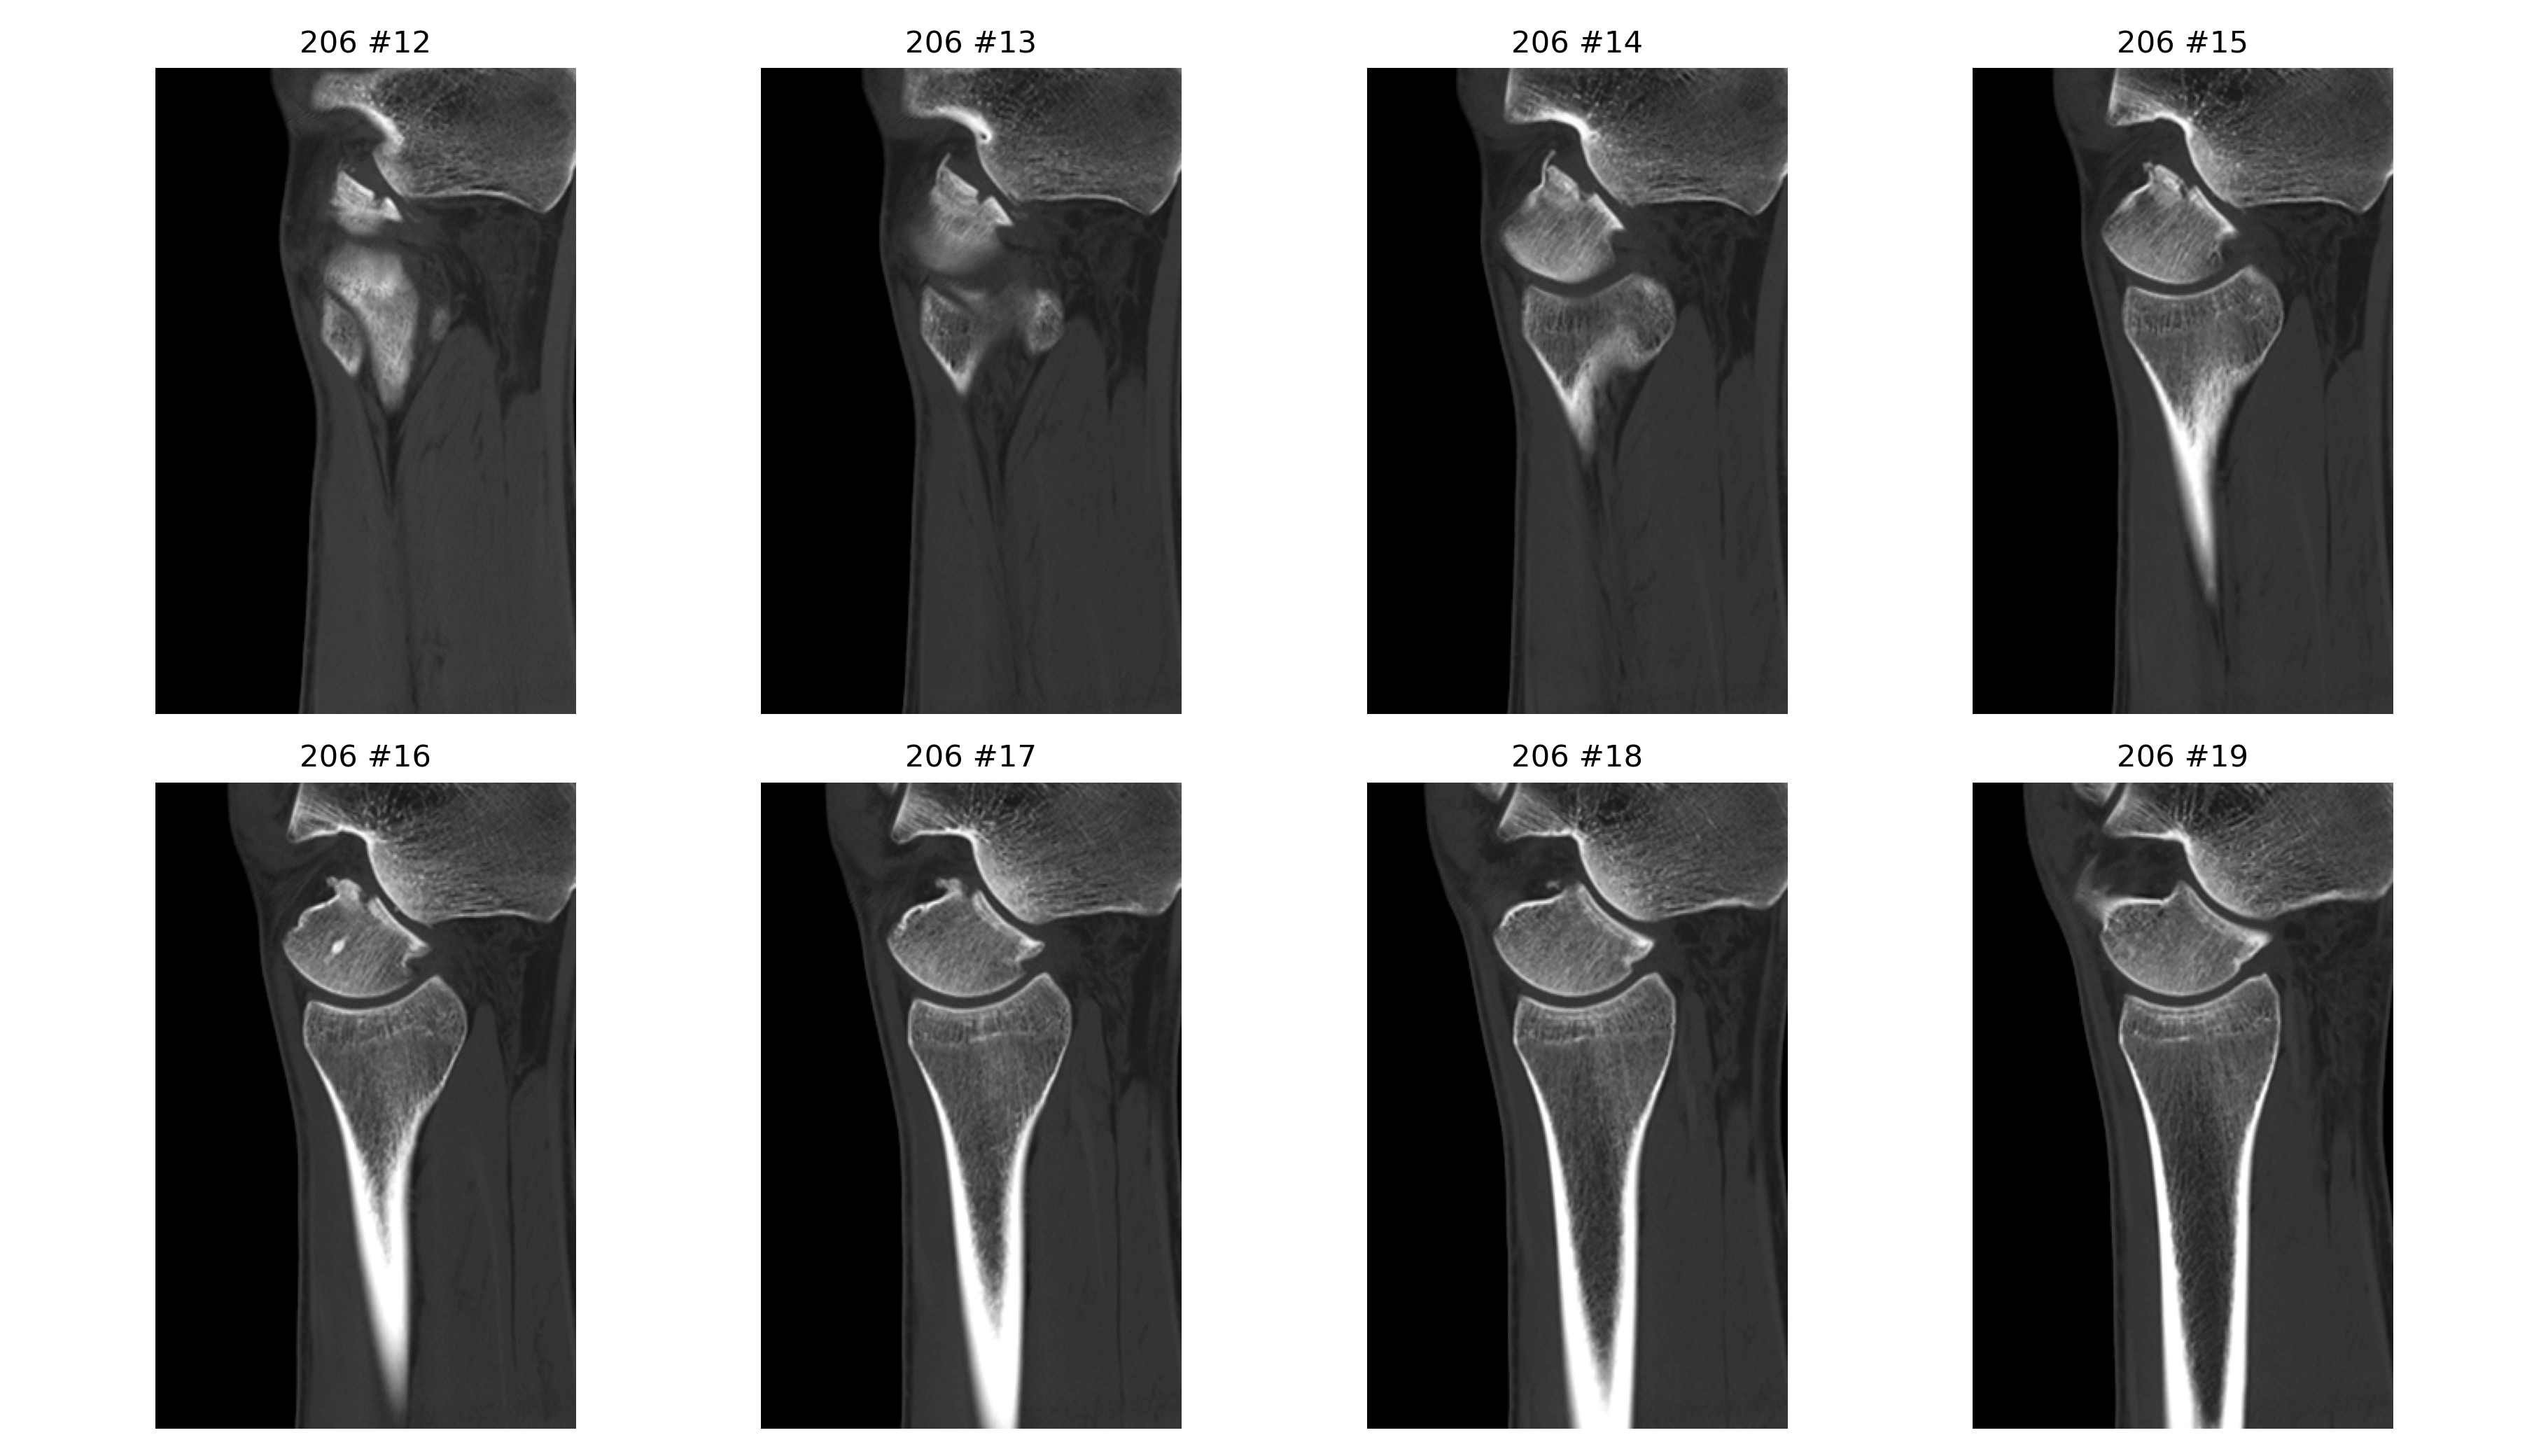

基于 2026-04-02 右踝无对比 CT 原始 DICOM 的辅助分析。核心问题是: 右踝外侧、距骨外侧突及距下关节外侧附近存在高概率关节内骨性损伤, 表现更接近单板滑雪常见的 snowboarder’s fracture。

- 冠状位、矢状位和三维辅助重建里都能反复看到局部骨性不规则和分离感。

三维与关键切面

三维图更适合看骨片和关节面的空间关系;真正判断骨折线、关节面台阶和位移, 仍然要以原始 CT 切面为主。

定量分析与标注图

以下毫米值为近似测量值,作用是帮助沟通位移量级,不等同于医生在工作站上的正式卡尺读数。